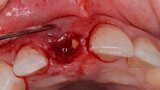

Figura 5. Hundimiento de la zona estética anterior inmediatamente después de la extracción del diente por la reabsorción de la pared vestibular.